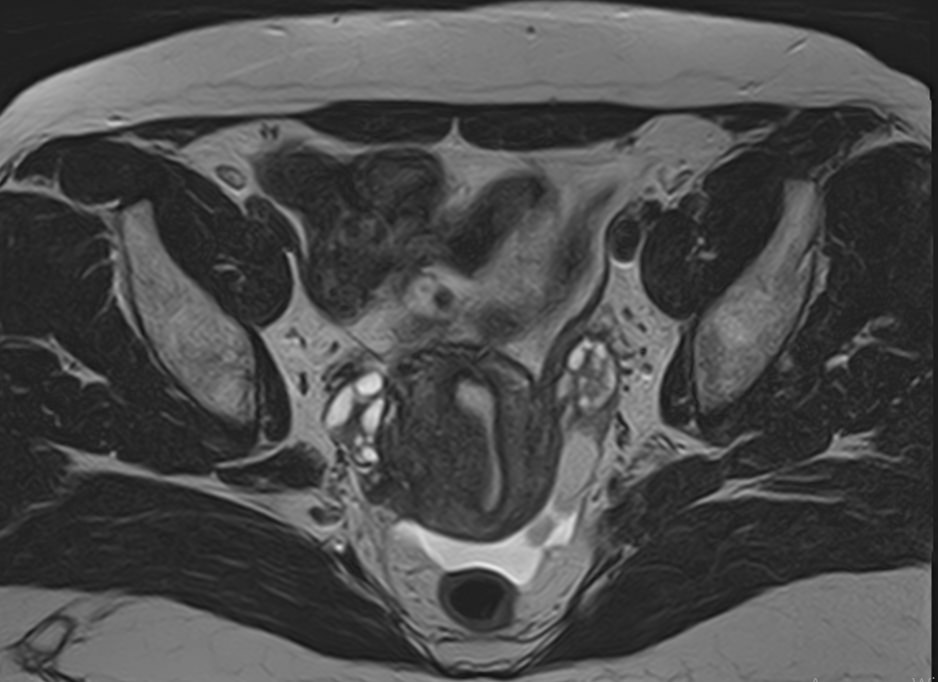

В нашей клинике магнитно-резонансная томография матки проводится при помощи новейшего томографа экспертного уровня TOSHIBA VANTAGE TITAN 1,5 Тесла. Высокая индукция магнитного поля томографа обеспечивает превосходную четкость и детализацию изображений органов женской репродуктивной системы. Отсутствие вредного рентгеновского излучения делает процедуру безопасной и дает возможность проведения исследования неоднократно по мере необходимости.

Наиболее часто томографию матки применяют в комплексной диагностике и лечении новообразований. Процедура позволяет с высокой точностью определить локализацию, размеры и влияние опухоли на окружающие ткани, а также провести первичную дифференциацию добро- и злокачественных структур (по форме, строению, особенностям накопления контраста и пр.). Динамический контроль методом МРТ позволяет объективно оценить эффективность терапевтической тактики.